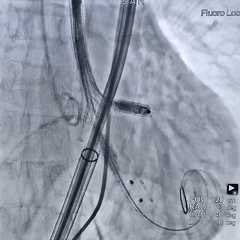

瓣膜缓慢释放至全展开